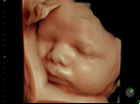

4D 超音波診断エコー

当クリニックで導入している最新式の3D/4Dエコー検査機は お腹の中の赤ちゃんの背伸びをしたりあくびをしたり指しゃぶりをしたり等の様子をリアルタイムに立体画像で見ることが可能です。

映像はSDカードに記録していきます。

お子様の胎内での成長過程を このすばらしい画像で記念に残してあげて下さい。

尚、赤ちゃんの姿勢や向きによってお顔などが十分に見られない時もありますのでご了承下さい。

- 最新機種で最上位機種の産婦人科向け超音波画像診断装置「Voluson E10」を導入致しております。

リアリティのある透明感と立体感を実現して、命の躍動をクリアに描き出します。